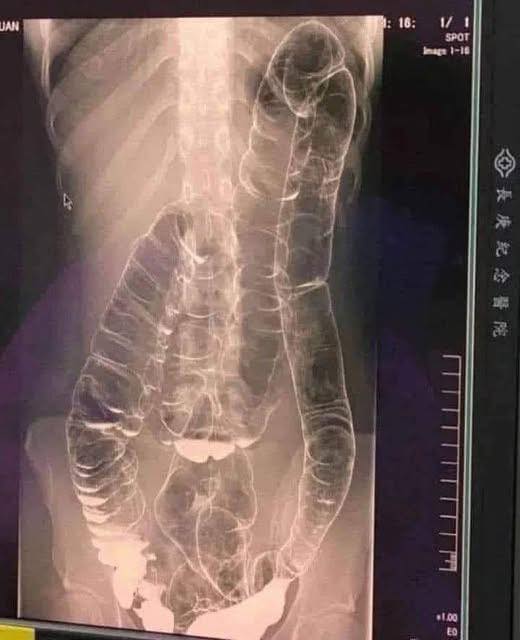

Constipação prolongada pode ser mais séria do que você imagina. Entenda os riscos do cólon saturado e saiba como prevenir a constipação.